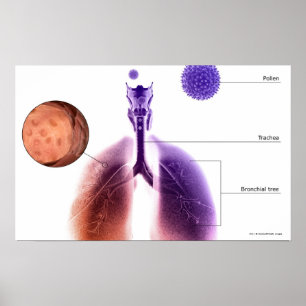

Illustration av en astmaattack från pollen poster

Pris343,00 kr